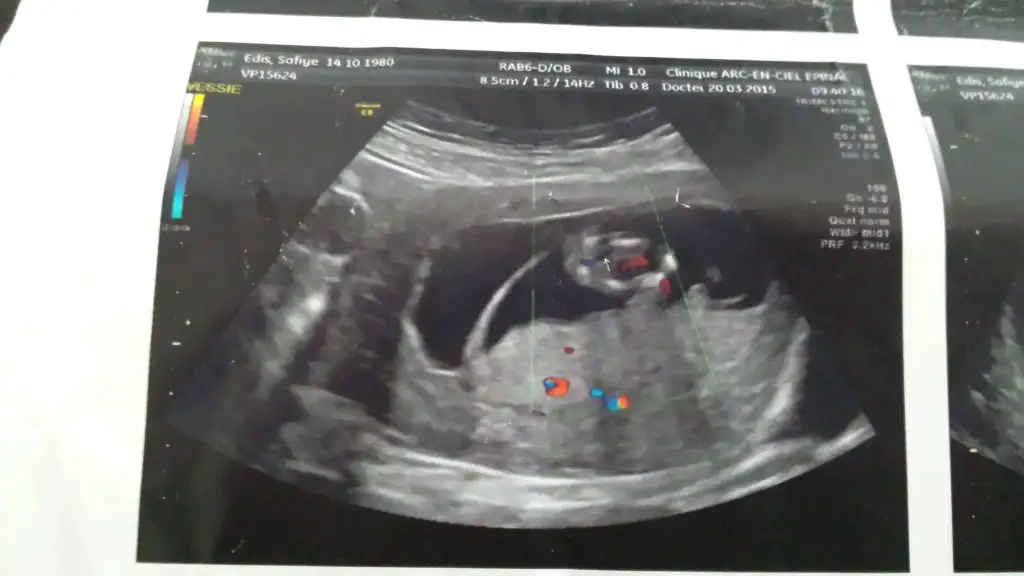

Erkeğe daha çok benzettim ikinci resimden dolayı. Ama kesin diyemem.Kızlar cinsiyet konusunda tahmin alabilirmiyim??Eki Görüntüle 1522208 Eki Görüntüle 1522219

Teşekkür ederim ben yurt dışındayım ama ultrasonda fark olurmu bilmiyorum en belirgin resmi diye koymuştum başka resim yükleyim , yorumun için çok sağol canımErkeğe benziyor ama çok değişik bir ultrason Fotoğrafı.

BANA YORUM YOKMU KIZLAR11 + 0 haftalık bebeğim yorum alabilirmiyiz

Henüz nubu oluşmamış bu teori için 12-13 haftalar en ideal zamanlar.

Bebeginiz erkek bence saglikli bi sekilde kucaginiza alin inss...